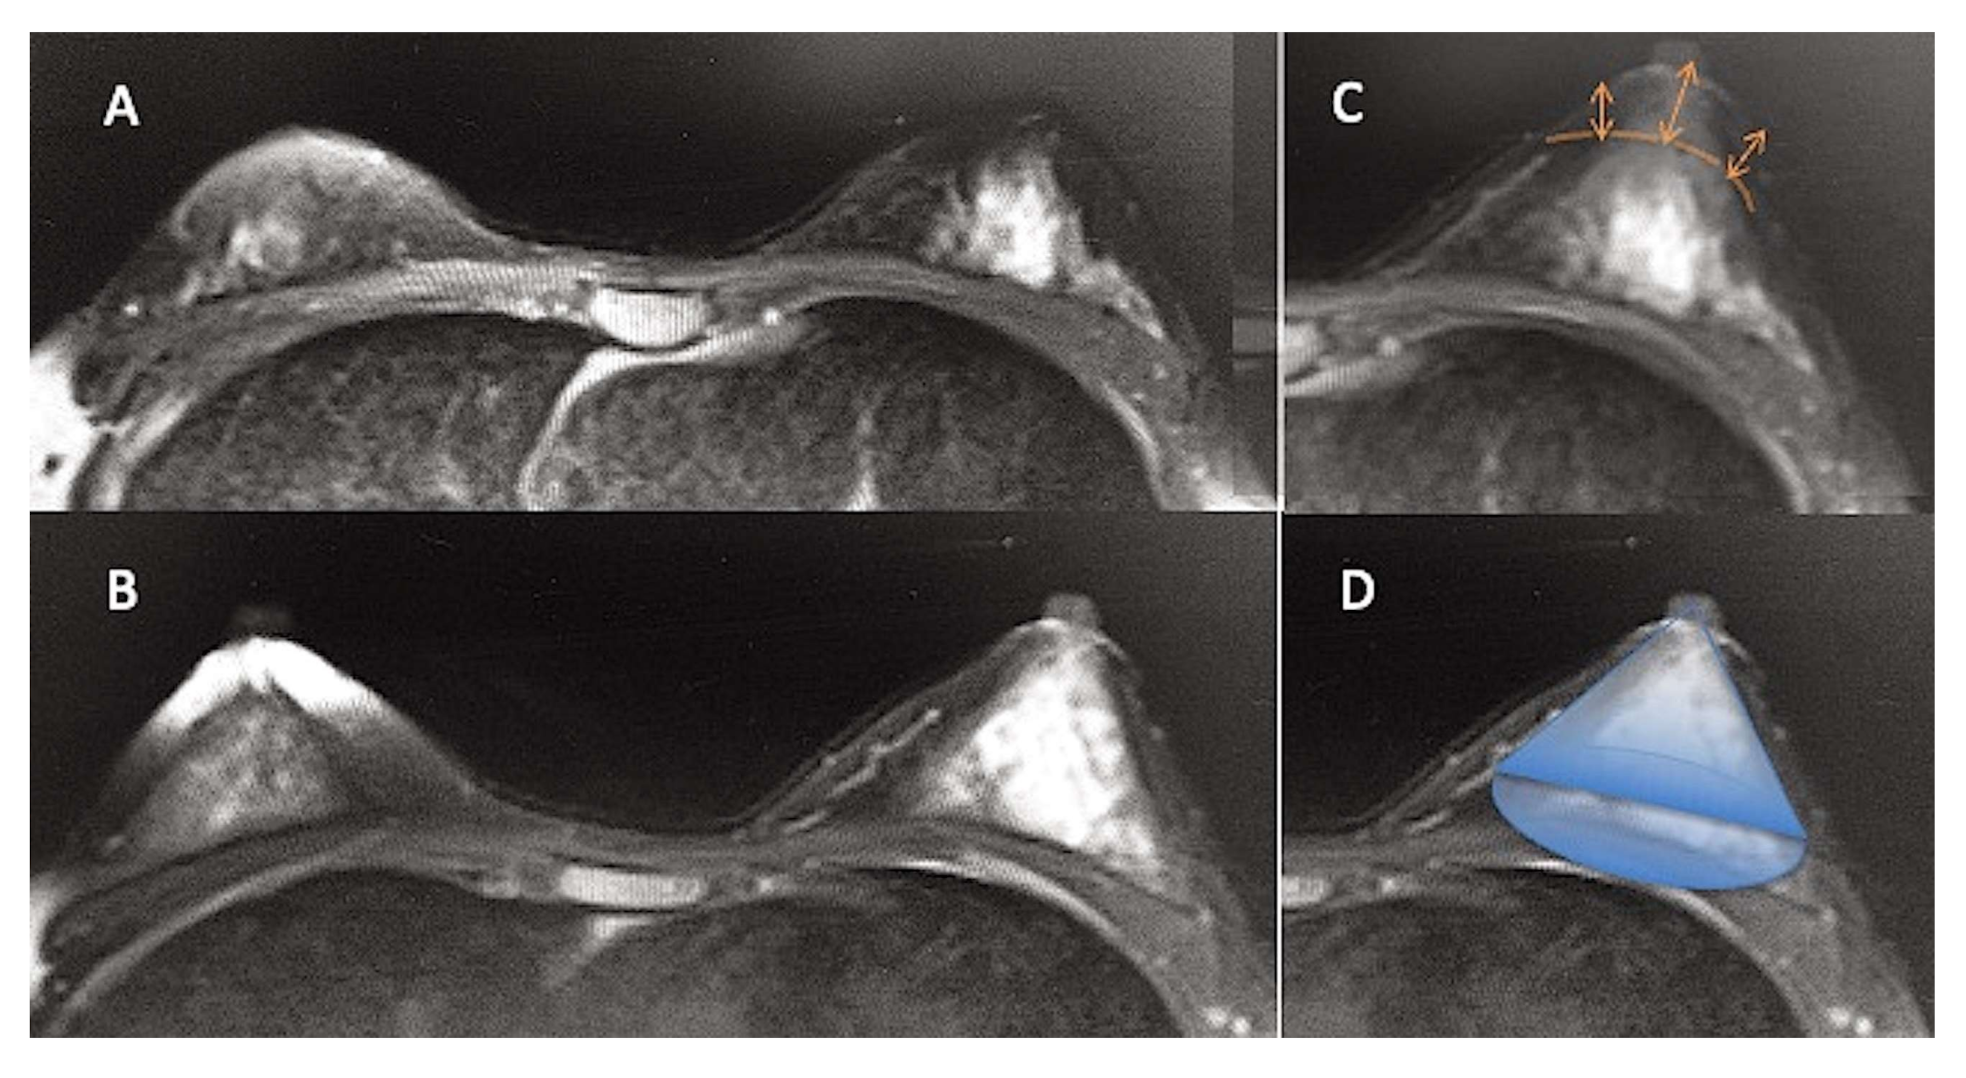

A careful anamnesis (patient’s expectations), a clinical evaluation (measurement of breast volume), pictures (hypoplasia and deformities evaluation), and an instrumental evaluation (MRI scans) (Figure 4A) were performed to estimate the optimal volume of fat to graft. A 1.5-Tesla MRI (Hitachi, MS, Echelon Oval, Tokyo, Japan) was used to produce 3-mm-thick slice images, analyzed by OsiriX software, 32 bits, free version (Pixmeo, CA), to calculate breast volume. Two calculations were conducted per examination, and the determined average was taken as the final breast volume. Based on the acquired MRI scans, volumetric fat site assessments of the breasts were also calculated, utilizing as edges the anterior axillary line, anterior margin of the pectoral muscle, Medio-sternal line, skin, and nipple. They were analyzed on a separate workstation (ADW 4.0; GE Medical Systems, Milwaukee, WI, USA) employing a 3D reconstruction. Every breast was considered a geometric “cone” (Figure 4D), and, for this reason, the formula Volume = π × r2 × h / 3 (base area per height, divided by 3) to evaluate the initial breast volume and the optimal volume of fat to inject into it was applied [2], to convert the initial amount of fat in milliliters to a volume expressed in cm3 [2]. (For example, in a breast with a radius (r) of 6 cm and height (h) 5 cm, Cone Volume = 3.14 × 36 × 5= 565.2 / 3 = 188.4 cm3. Thus, the amount of fat graft injected will be 188.4 mL).

Figure 4. Magnetic resonance imaging (MRI) of a patient treated with AFG. (A) The pre-operative situation in a patient affected by bilateral breast hypoplasia. (B) The post-operative situation at T5 (6 months) after one AFG treatment with an evident improvement of bilateral breast volume. (C) Overlapping of pre-and post-op MRI images with the volume increase measurement detail of 29.5 mm (arrows). (D) Overlapping of a geometric cone on augmented breast to note the similar aspect of the breast to a cone.